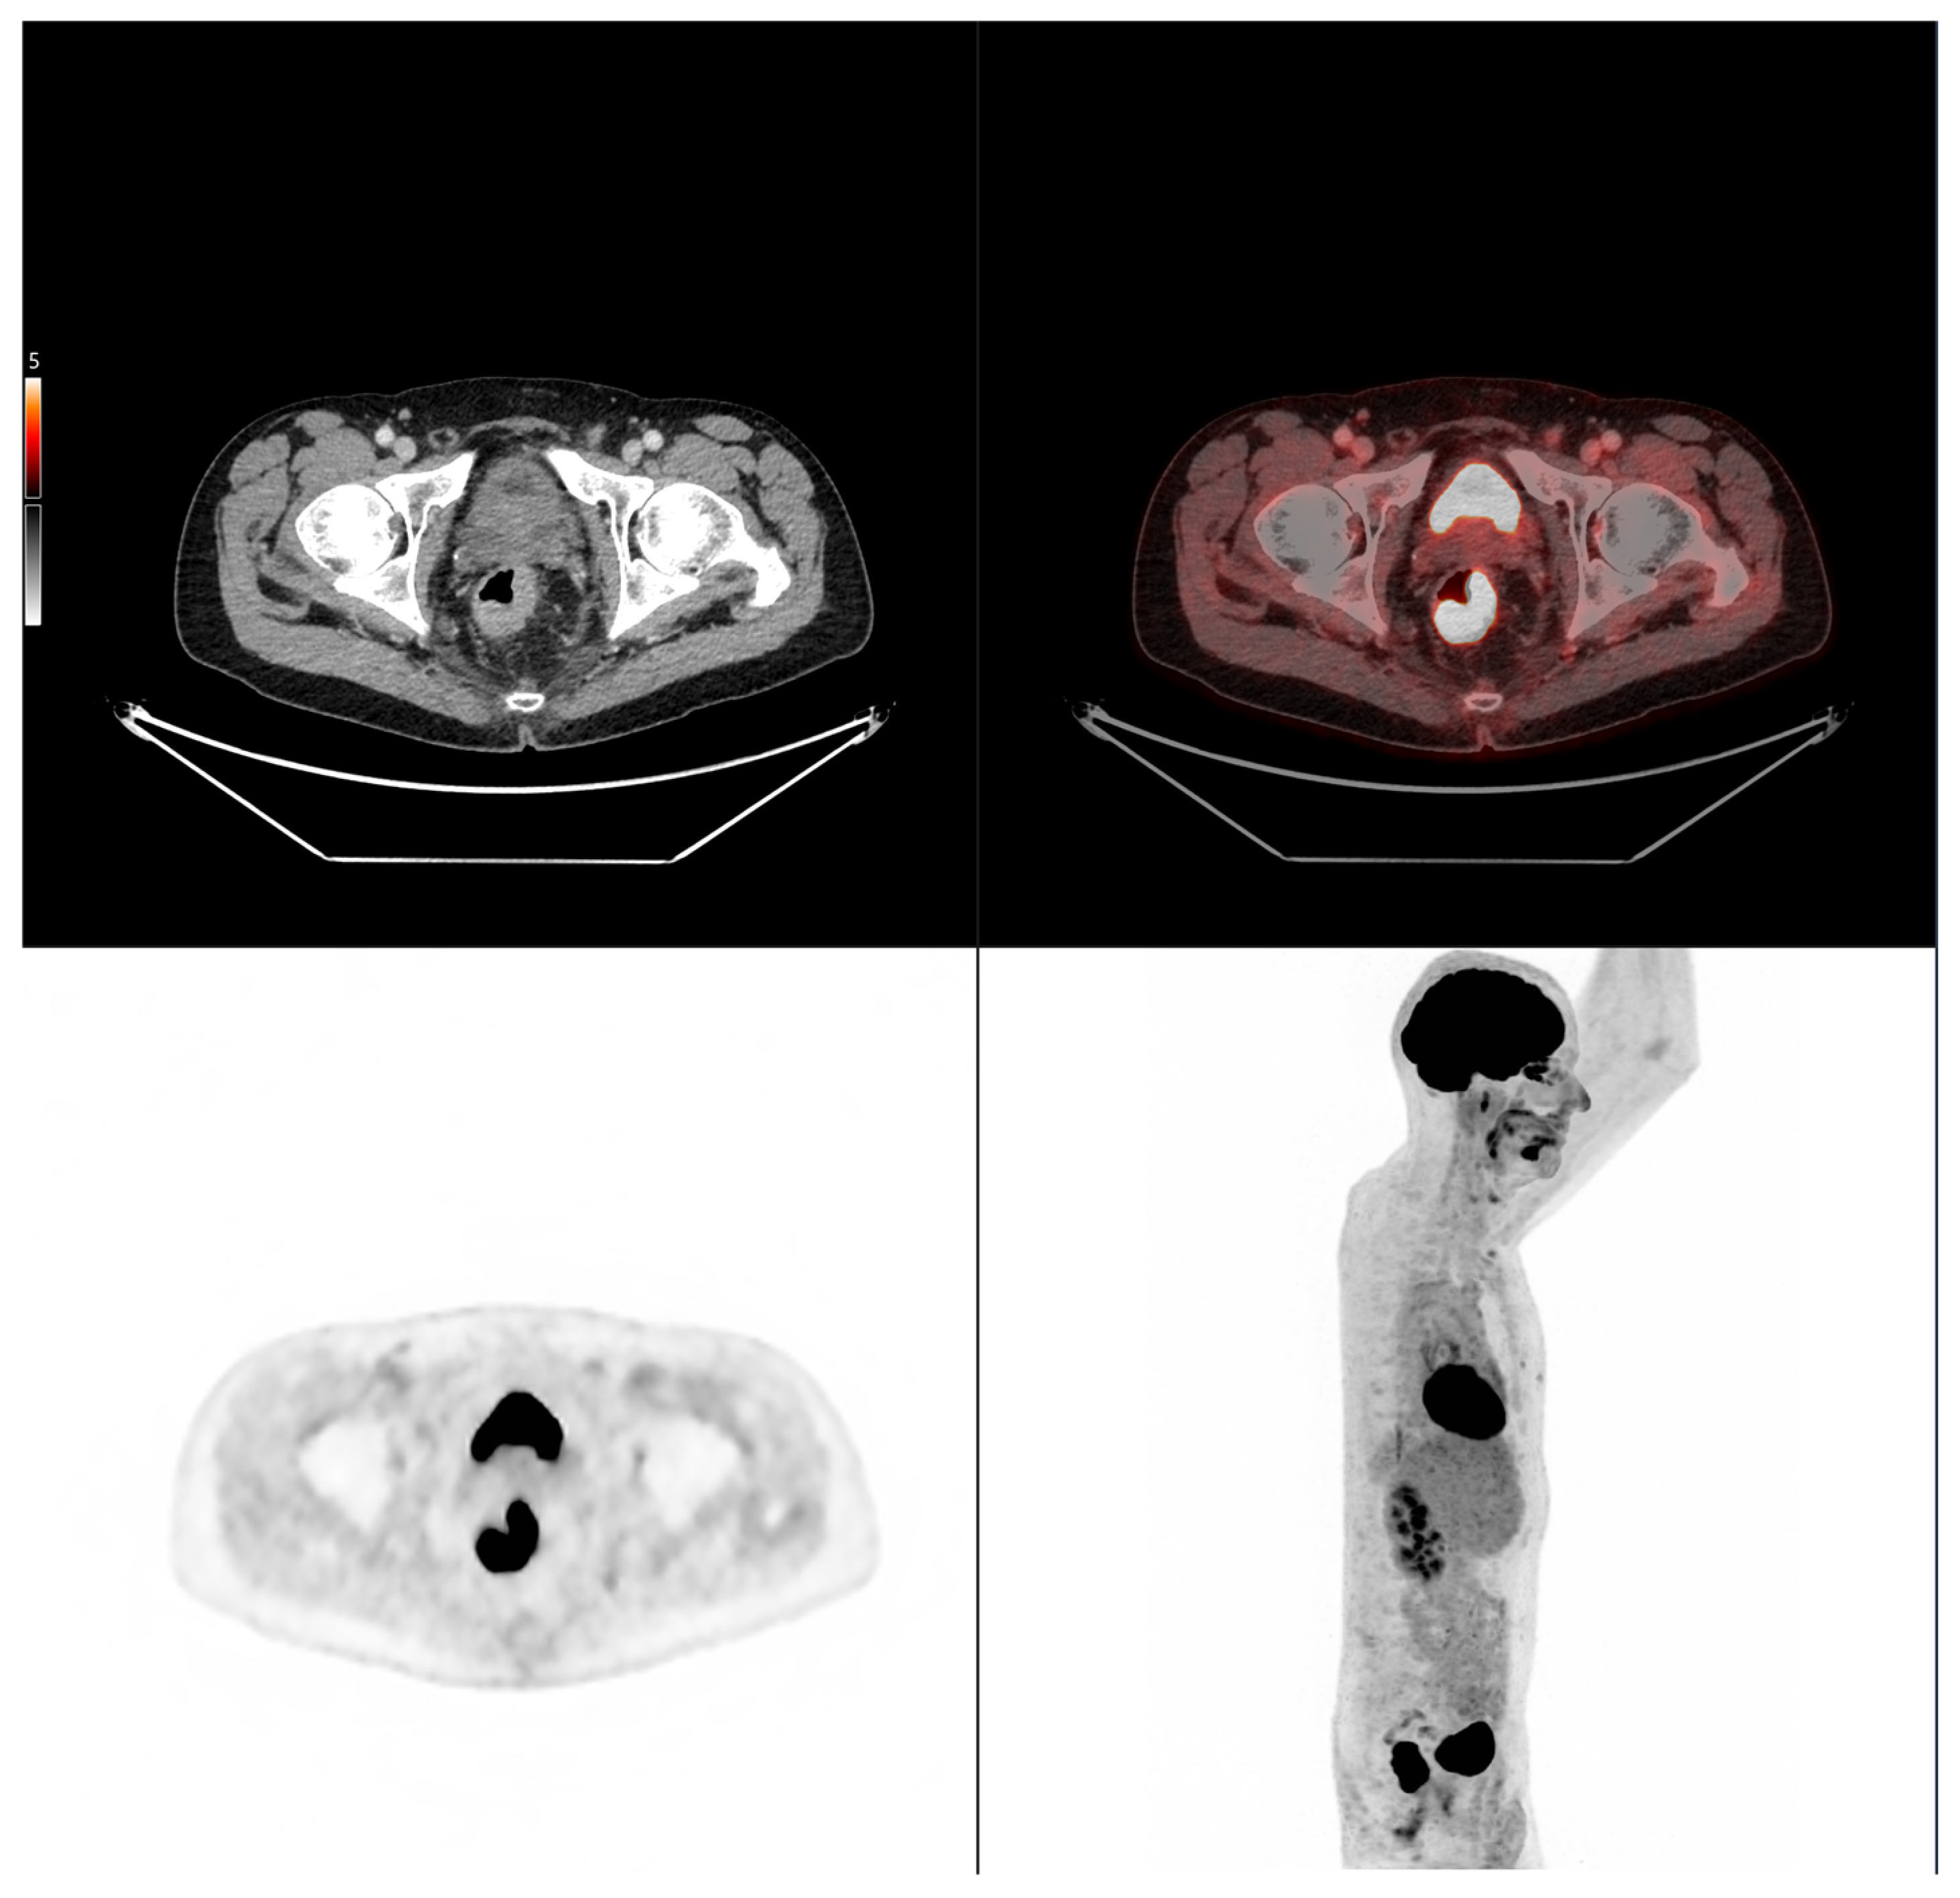

Altogether, these analyses demonstrate that MTV of the primary tumor is a consistent predictor of both OS and PFS. While OS was primarily influenced by sex and MTV, PFS was more strongly determined by UICC stage and MTV, as displayed in Figure 6. For a clearer understanding of the presented results, Figure 7 shows a representative example of manual delineation of the primary tumor on baseline FDG PET/CT.

Figure 7.

Representative example of manual delineation of a primary rectal tumor on baseline FDG PET/CT showing manual delineation of the metabolically active tumor volume (first row) on the PET image with corresponding fused PET/CT image and CT image with iodinated contrast medium (second row). Morphological features, including tumor shape (circular or semi-circular), cranio-caudal extension (in cm), and overall tumor volume (in cm3), were assessed on the CT image (often with contrast medium) coregistered with the PET images. Tumor shape was determined on the axial plane, cranio-caudal extension on the sagittal plane, and tumor volume after careful delineation on all planes. Iodinated contrast medium was administrated in 70% of cases after exclusion of contraindications. Metabolic parameters, including SUVmax, SUVmean, MTV and TLG, were systematically extracted from the segmented tumor (yellow in this figure). SUVmax (M in this figure) and TLG were automatically displayed. SUVmean could be obtained by simply replacing SUVmax with SUVmean in the parameter selection. MTV was automatically calculated from TLG and SUVmean values displayed on the workstation. The highlighted region in yellow represents the 3D contour of the primary tumor, excluding physiological uptake and non-tumor regions.

Case 2: A 69-year-old patient with stage IIA rectal cancer, presenting with a semi-circumferential primary tumor with craniocaudal extension and MTV both below the predictive cut-offs (5.1 cm vs. 6.2 cm; MTV 10.1 vs. 35.49 for OS and 32.08 for PFS). Baseline FDG PET/CT (top row) revealed intense hypermetabolism (SUVmax 38.8). Interim FDG PET/CT (bottom row) showed a good partial metabolic response, and the patient experienced sustained clinical benefit with no progression in the long term (OS = PFS = 29 months).